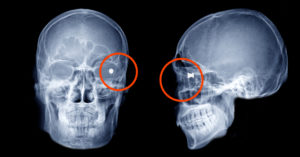

Вот, например, казус Алексея Алферова, о котором рассказал телеграм-канал Mash. Он родился в Казахстане, а учиться приехал в Москву и жил, соответственно, в общежитии. Как-то в 2003 году он заглянул на огонек в комнату другого студента, Евгения. Тот — так уж вышло — в этот момент разбирал пневматический пистолет и случайно нажал на спуск. Оставим в стороне вопрос, почему Евгений разбирал заряженный пистолет (по технике безопасности этого делать нельзя), но пуля вылетела из ствола и попала гостю прямо в глазницу. По счастливой случайности глаз остался цел. Алексей никому об этом случае сообщать не стал: то ли друга сдавать не хотел, то ли проверок боялся.

Теперь Алексею 35, он живет в частном доме в Новой Москве, и о прошлом ему напоминает только пуля в голове. Жить она ему все это время не мешала, пока не возникла необходимость сделать процедуру МРТ, и медики сказали, что с пулей ее провести невозможно. Сейчас мужчину готовят к операции, а полиция, несмотря на давность случая, проводит проверку.